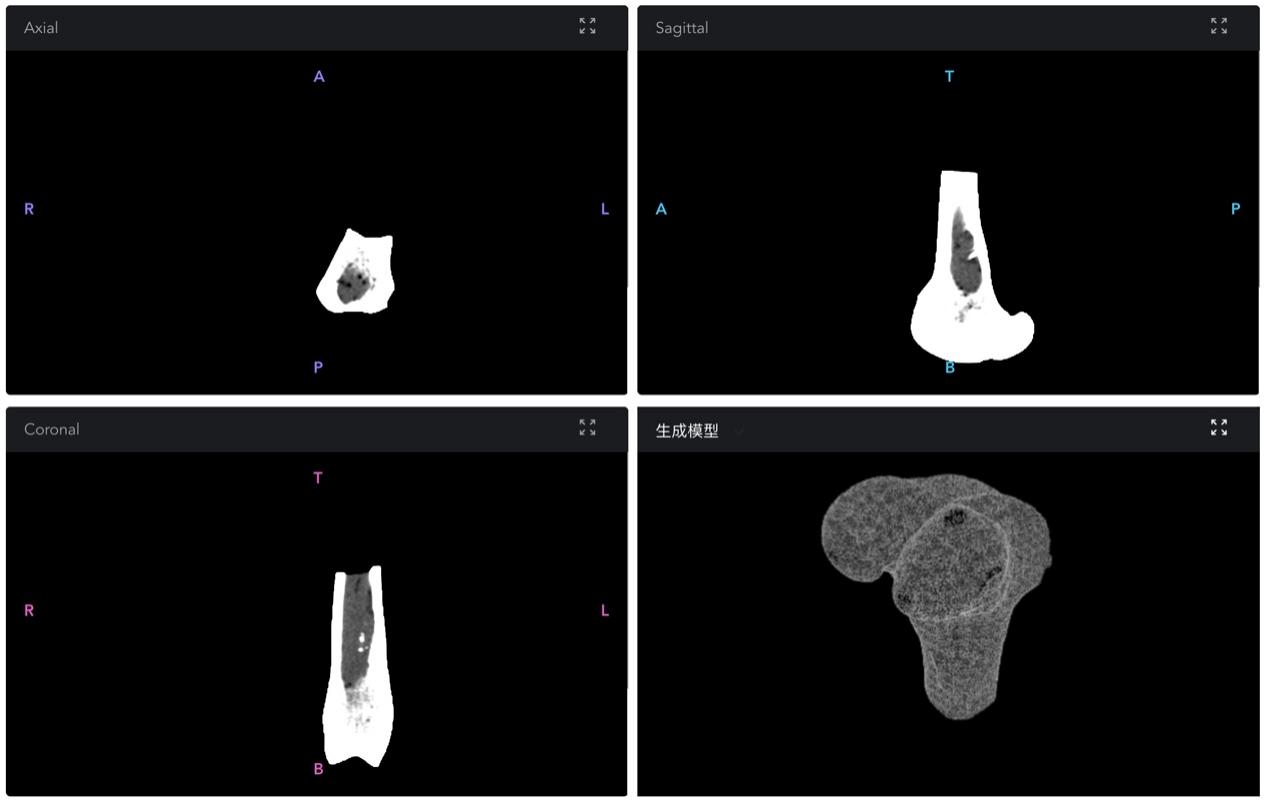

图1 缺损部位镜像CT影像切片及智能设计结果可视化展示

该技术是由航院庄茁教授团队以“FEM+AI”先进计算软件为核心开发的智能化骨修复体定制设计平台,可用于智慧医疗的个性化骨修复体快速设计制造,为传统定制化骨植入器械治疗手段中设计耗时长、成本昂贵、性能不匹配等夹脖子难题提供了全新解决方案。

该团队综合运用深度学习、强化学习等人工智能技术,完成从患者临床CT影像,到定制化生成骨植入器械3D打印模型的端到端工作流创建,大大缩减了个性化假体骨设计的时间和成本,为骨缺损患者,特别是重大创伤后造成骨缺损,以及骨再生能力较弱,急需救治手术的患者群体提供了全新的医疗解决方案和思路。主要突破进展体现在以下三方面: